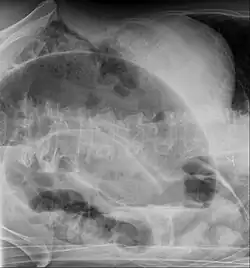

-

Coffee bean sign in a person with sigmoid volvulus -

Coronal view of sigmoid volvulus with "whirlpool sign" -

CT scan of a small bowel volvulus. It shows two juxtaposed segments of narrowing, which is the spot of mesentery rotation. The other signs indicate strangulation. -

An x-ray of a person with a small bowel volvulus.